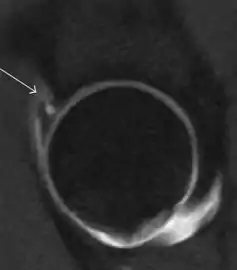

Synovial chondromatosis can be confidently diagnosed by X-ray when calcified cartilaginous chondromas are seen. However, other synovial proliferative processes, such as pigmented villonodular synovitis, require MRI for accurate diagnosis, although noncalcified synovitis can be suspected in radiographs by indirect signs, such as soft tissue swelling and/or erosions in the femoral head, femoral neck, or acetabulum (Figure 7).[1]

Figure 7:

Sagittal T2* gradient echo image showing a posterior soft tissue mass with hypointense areas secondary to hemosiderin deposition.[1]

In synovial proliferative disorders, MRI demonstrates synovial hypertrophy. In the case of PVNS, characteristic foci of low signal intensity related to hemosiderin deposition are better seen on gradient echo T2* images (Figure 7). In the case of synovial osteochondromatosis, the synovial hypertrophy is accompanied by intermediate signal cartilaginous loose bodies and/or low signal calcified loose bodies.[1]